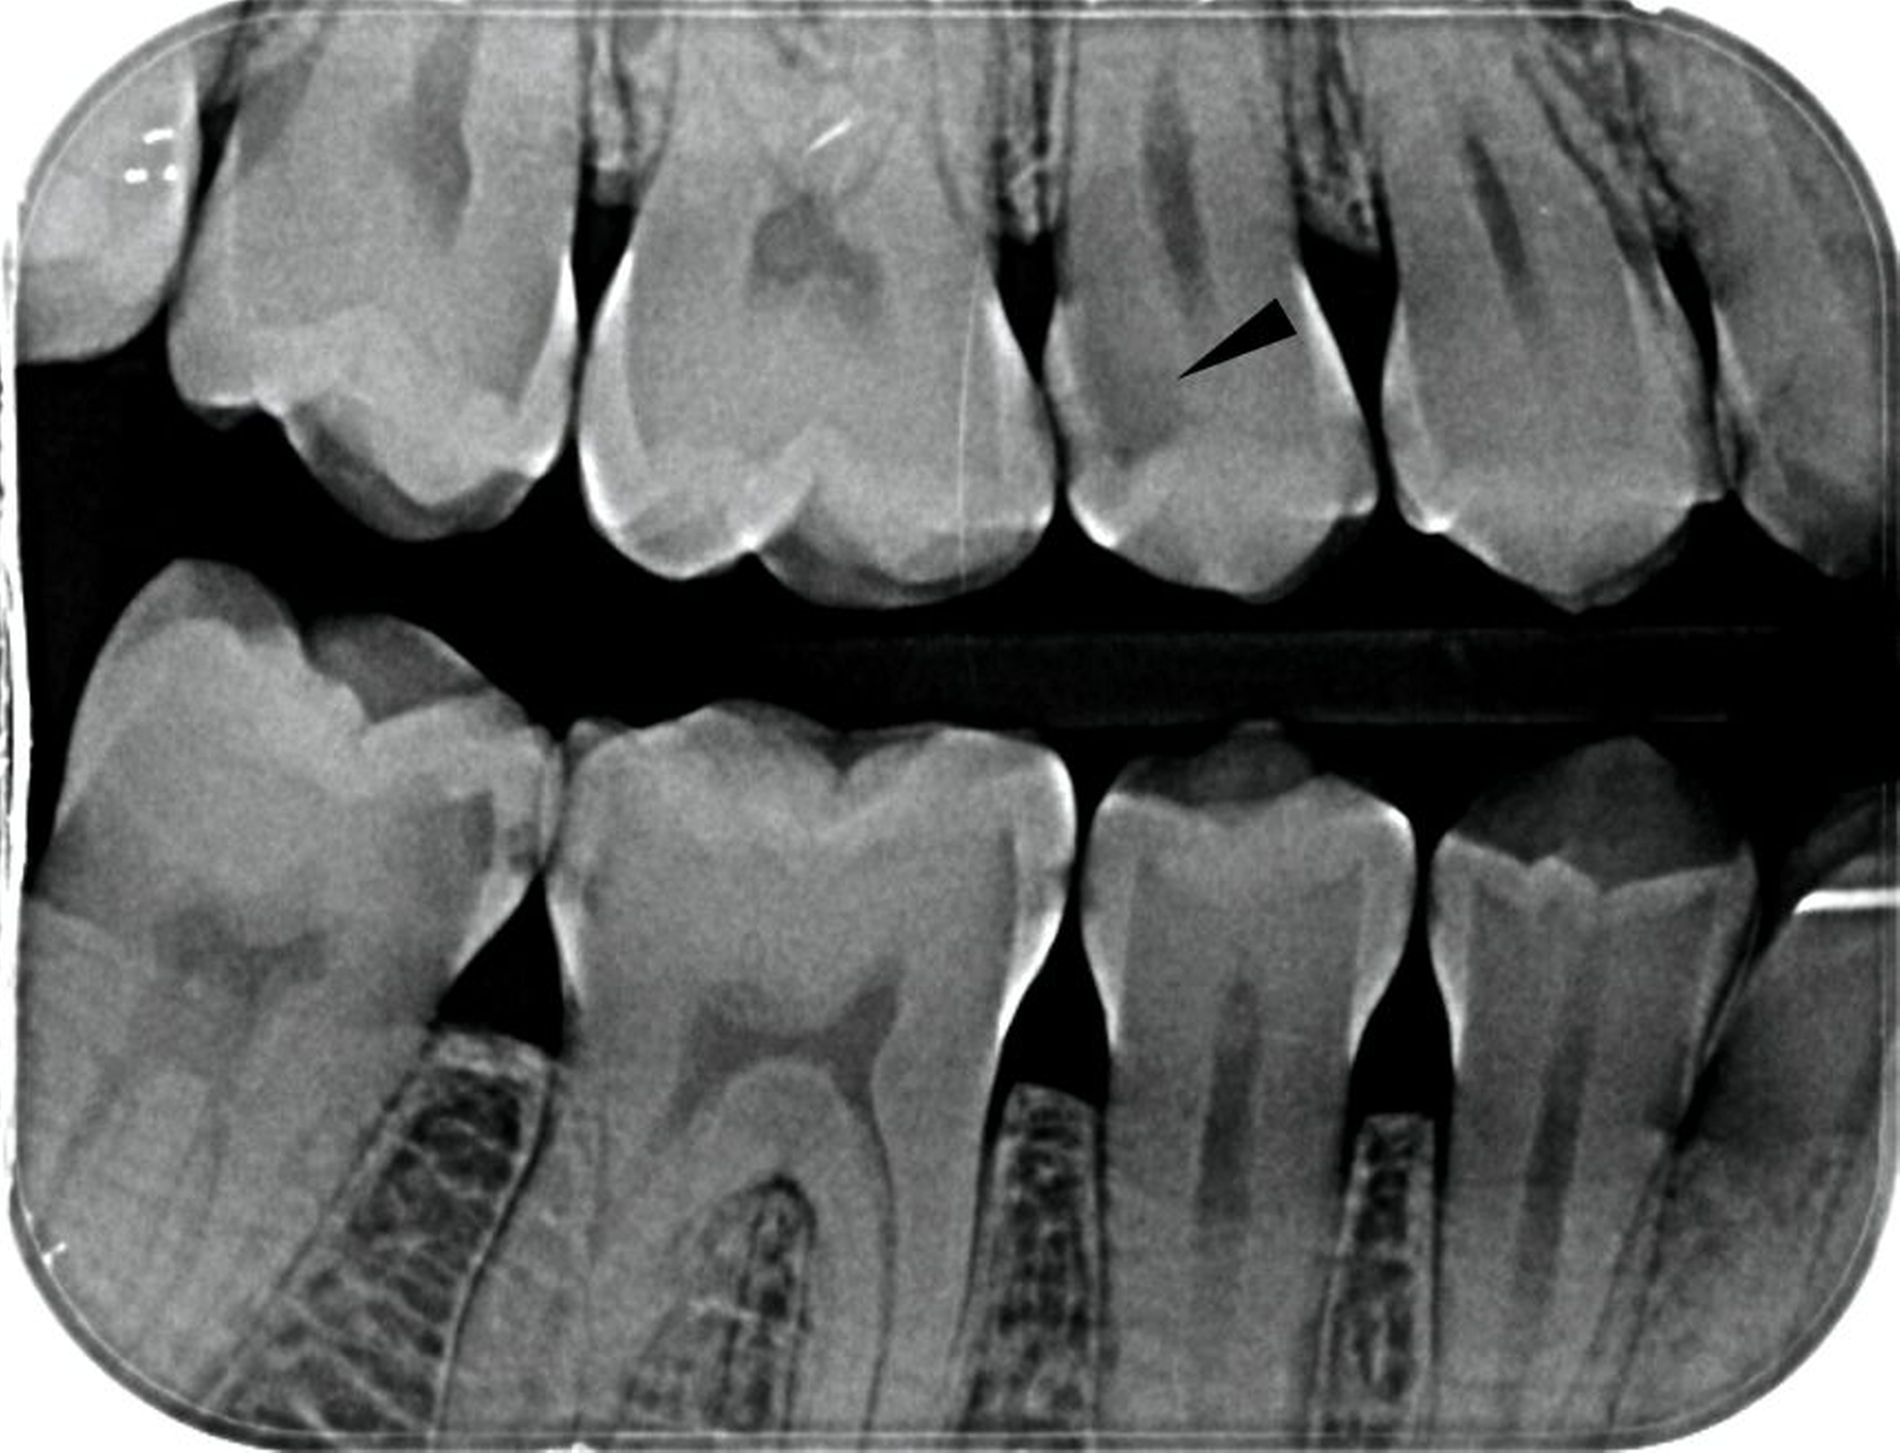

Grundsätzlich stellt sich die Frage nach einem spezifisch angepassten (selektiven) Endpunkt der Kariesentfernung im Wesentlichen nur bei pulpanahen kariösen Läsionen, die – wie in den Abbildungen 1 und 2 – röntgenologisch eine Ausdehnung bis ins innere Dentindrittel oder -viertel aufweisen. Bei einer geringeren Ausdehnung bis maximal ins mittlere Dentindrittel (Abbildung 1A, weißer Pfeil) ist hingegen eine nicht-selektive Kariesentfernung bis ins harte Dentin angezeigt [Schwendicke et al., 2021]. Ziel ist es, das Risiko der artifiziellen Pulpaeröffnung zu reduzieren und die Pulpaintegrität zu schützen, da die Eröffnung der Pulpa im Rahmen der Kariesentfernung mit einer deutlich schlechteren Prognose für den Vitalerhalt einhergeht [Bjørndal et al., 2010]. Die non-selektive Entfernung kariös veränderten Dentins bis zum Endpunkt „hartes Dentin“ wird daher inzwischen bei tiefen Läsionen ohne klinische Symptome von einigen Autoren als Übertherapie eingestuft [Carvalho, 2023; Widbiller et al., 2022].

Bei der Definition des Endpunkts der selektiven Kariesentfernung gibt es Unterschiede, die je nach Arbeitsgruppe variieren. Die hierzulande gängige Beschreibung definiert die non-selektive Kariesentfernung als Entfernung von erweichtem und festem kariös verändertem Dentin sowohl in peripheren als auch in zentralen beziehungsweise pulpanahen Bereichen der Kavität (Abbildung 1). Als Endpunkt gilt dabei „hartes Dentin“ [Widbiller et al., 2022; Schwendicke/Göstemeyer, 2016]. Im Unterschied dazu verbleibt bei der selektiven Kariesentfernung pulpanah festes (mit Handexkavator schneidbares) oder weiches Dentin (Abbildungen 1B distal und Abb. 3 schwarzer Pfeil). Peripher wird das Dentin bis zur Sondenhärte entfernt (Abbildung 3, weißer Pfeil), bevor die Kavität anschließend direkt mit einer definitiven adhäsiven Restauration versorgt wird (Abbildung 4) [Widbiller et al., 2022].